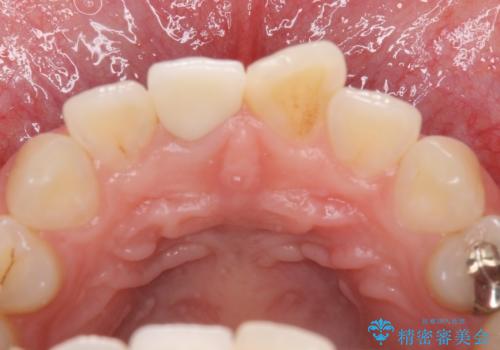

- 患者様は、他院にて5年前に前歯の神経をとってから、変色が気になり出したとのことでご来院されました。

セラミックのみも可能でしたが、念のため根管治療からのやりかえをご希望されました。

歯は神経をとると、だんだん黒くなることがあります。今回はセラミックで歯を覆うことにより、見た目の改善を図りました。